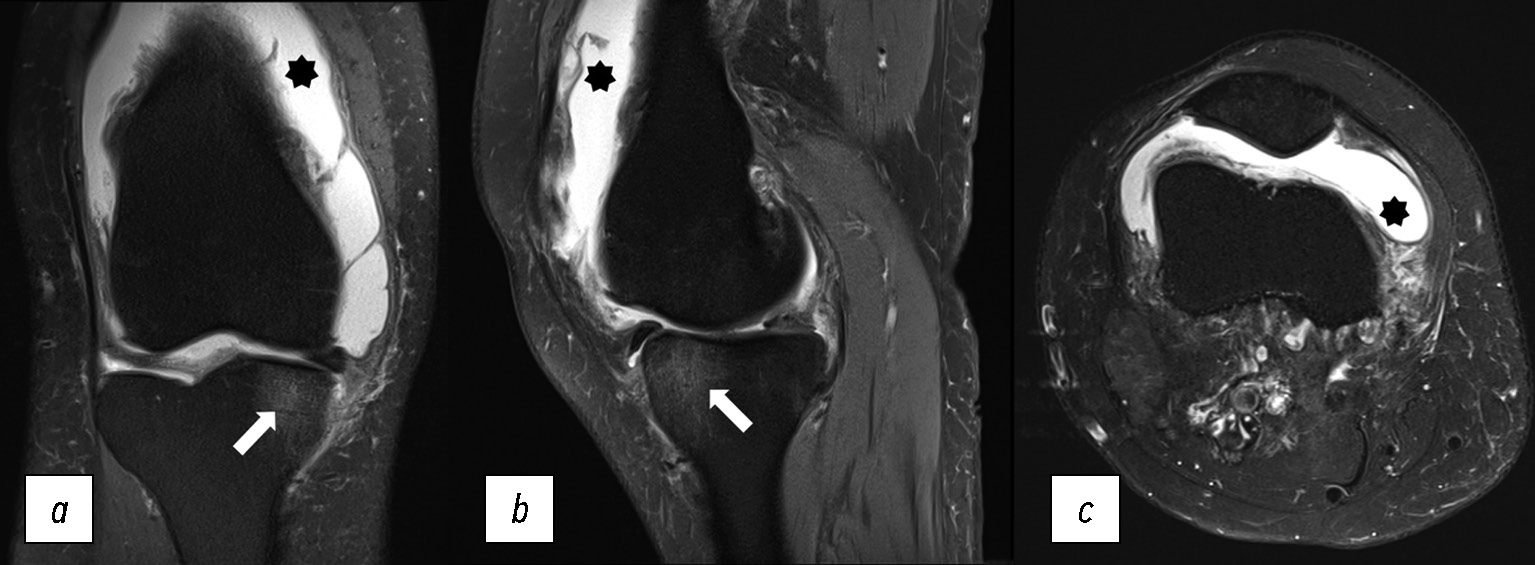

На МР-томограммах (рис. 10) выявлен равномерный, без каких-либо включений, отёк костного мозга в области внутреннего мыщелка большеберцовой кости, который сопровождался выраженным выпотом в полость коленного сустава и развитием воспаления окружающих мягких тканей.

Рис. 10. МР-томограммы коленного сустава: a, b, c — корональная, сагиттальная и аксиальная проекции в режиме PD FS с подавлением сигнала от жировой ткани при септическом артрите правого коленного сустава. Звёздочка — избыточное количество синовиальной жидкости в полости коленного сустава (синовит), стрелка — отёкоподобное усиление сигнала костного мозга внутреннего мыщелка правой большеберцовой кости.

Fig. 10. MRI scans of the knee: a, b, c — coronal, sagittal and axial views in to suppress the signal from adipose tissue with a septic arthritis right knee. Marks — excessive amount of synovial fluid in the volvulus of the knee joint (synovitis), arrow — edema-like marrow signal intensity (ELMSI) of the internal condyle of the right tibia.

Септический характер поражения подтверждается микробиологическим обследованием синовиальной жидкости и лабораторными показателями крови.

В ряде случаев при септическом артрите отёк костной ткани может быть с тотальным поражением бедренной и большеберцовой кости, как представлено на рис. 11, полученном у пациента с вторичной инфекцией после перенесённого COVID-19.